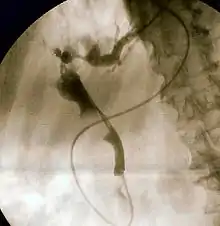

Endoscopic retrograde cholangiopancreatography (ERCP) is a technique that combines the use of endoscopy and fluoroscopy to diagnose and treat certain problems of the biliary or pancreatic ductal systems. It is primarily performed by highly skilled and specialty trained gastroenterologists. Through the endoscope, the physician can see the inside of the stomach and duodenum, and inject a contrast medium into the ducts in the biliary tree and pancreas so they can be seen on radiographs.

The patient is sedated or anaesthetized. Then a flexible camera (endoscope) is inserted through the mouth, down the esophagus, into the stomach, through the pylorus into the duodenum where the ampulla of Vater (the union of the common bile duct and pancreatic duct) exists. The sphincter of Oddi is a muscular valve that controls the opening to the ampulla. The region can be directly visualized with the endoscopic camera while various procedures are performed. A plastic catheter or cannula is inserted through the ampulla, and radiocontrast is injected into the bile ducts and/or pancreatic duct. Fluoroscopy is used to look for blockages, or other lesions such as stones.

When needed, the sphincters of the ampulla and bile ducts can be enlarged by a cut (sphincterotomy) with an electrified wire called a sphincterotome for access into either so that gallstones may be removed or other therapy performed.

Other procedures associated with ERCP include the trawling of the common bile duct with a basket or balloon to remove gallstones and the insertion of a plastic stent to assist the drainage of bile. Also, the pancreatic duct can be cannulated and stents be inserted. The pancreatic duct requires visualisation in cases of pancreatitis.